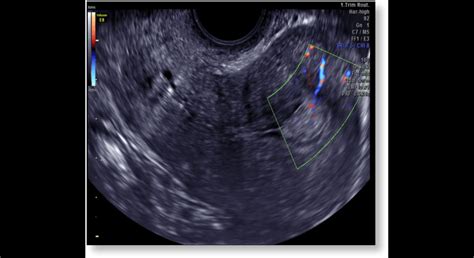

Hodnotenie hCG v krvi má význam nielen pri potvrdení tehotenstva, ale aj pri podozrení na mimomaternicové tehotenstvo, hroziaci potrat či zamlčaný potrat. Hladina hCG pri mimomaternicovom tehotenstve v prvých dňoch alebo týždňoch môže byť v normálnom rozmedzí. hCG test možno použiť na podozrenie pri abnormálnom tehotenstve od siedmeho-ôsmeho týždňa, pretože rýchlosť zvýšenia jeho hladiny je nižšia ako pri normálnom vývoji plodu. hCG test nie je spoľahlivou metódou diagnostiky mimomaternicového tehotenstva. Na určenie mimomaternicového tehotenstva je potrebné absolvovať gynekologický ultrazvuk. Ak hladina hCG naznačuje tehotenstvo, no na ultrazvuku sa nezobrazí oplodnené vajíčko, gynekológ diagnostikuje mimomaternicové tehotenstvo a predpíše liečbu.

Hodnoty hCG pri prerušenom tehotenstve sa časovo nezhodujú alebo drasticky klesajú, pretože embryo odumrelo a syntéza hormónu s placentou sa zastavila. Znížená hladina hCG môže naznačovať aj riziko potratu a vyžaduje si ďalšie testy a vyšetrenie gynekológom a pôrodníkom. Na diagnostiku prerušeného tehotenstva sa vykonáva gynekologický ultrazvuk.